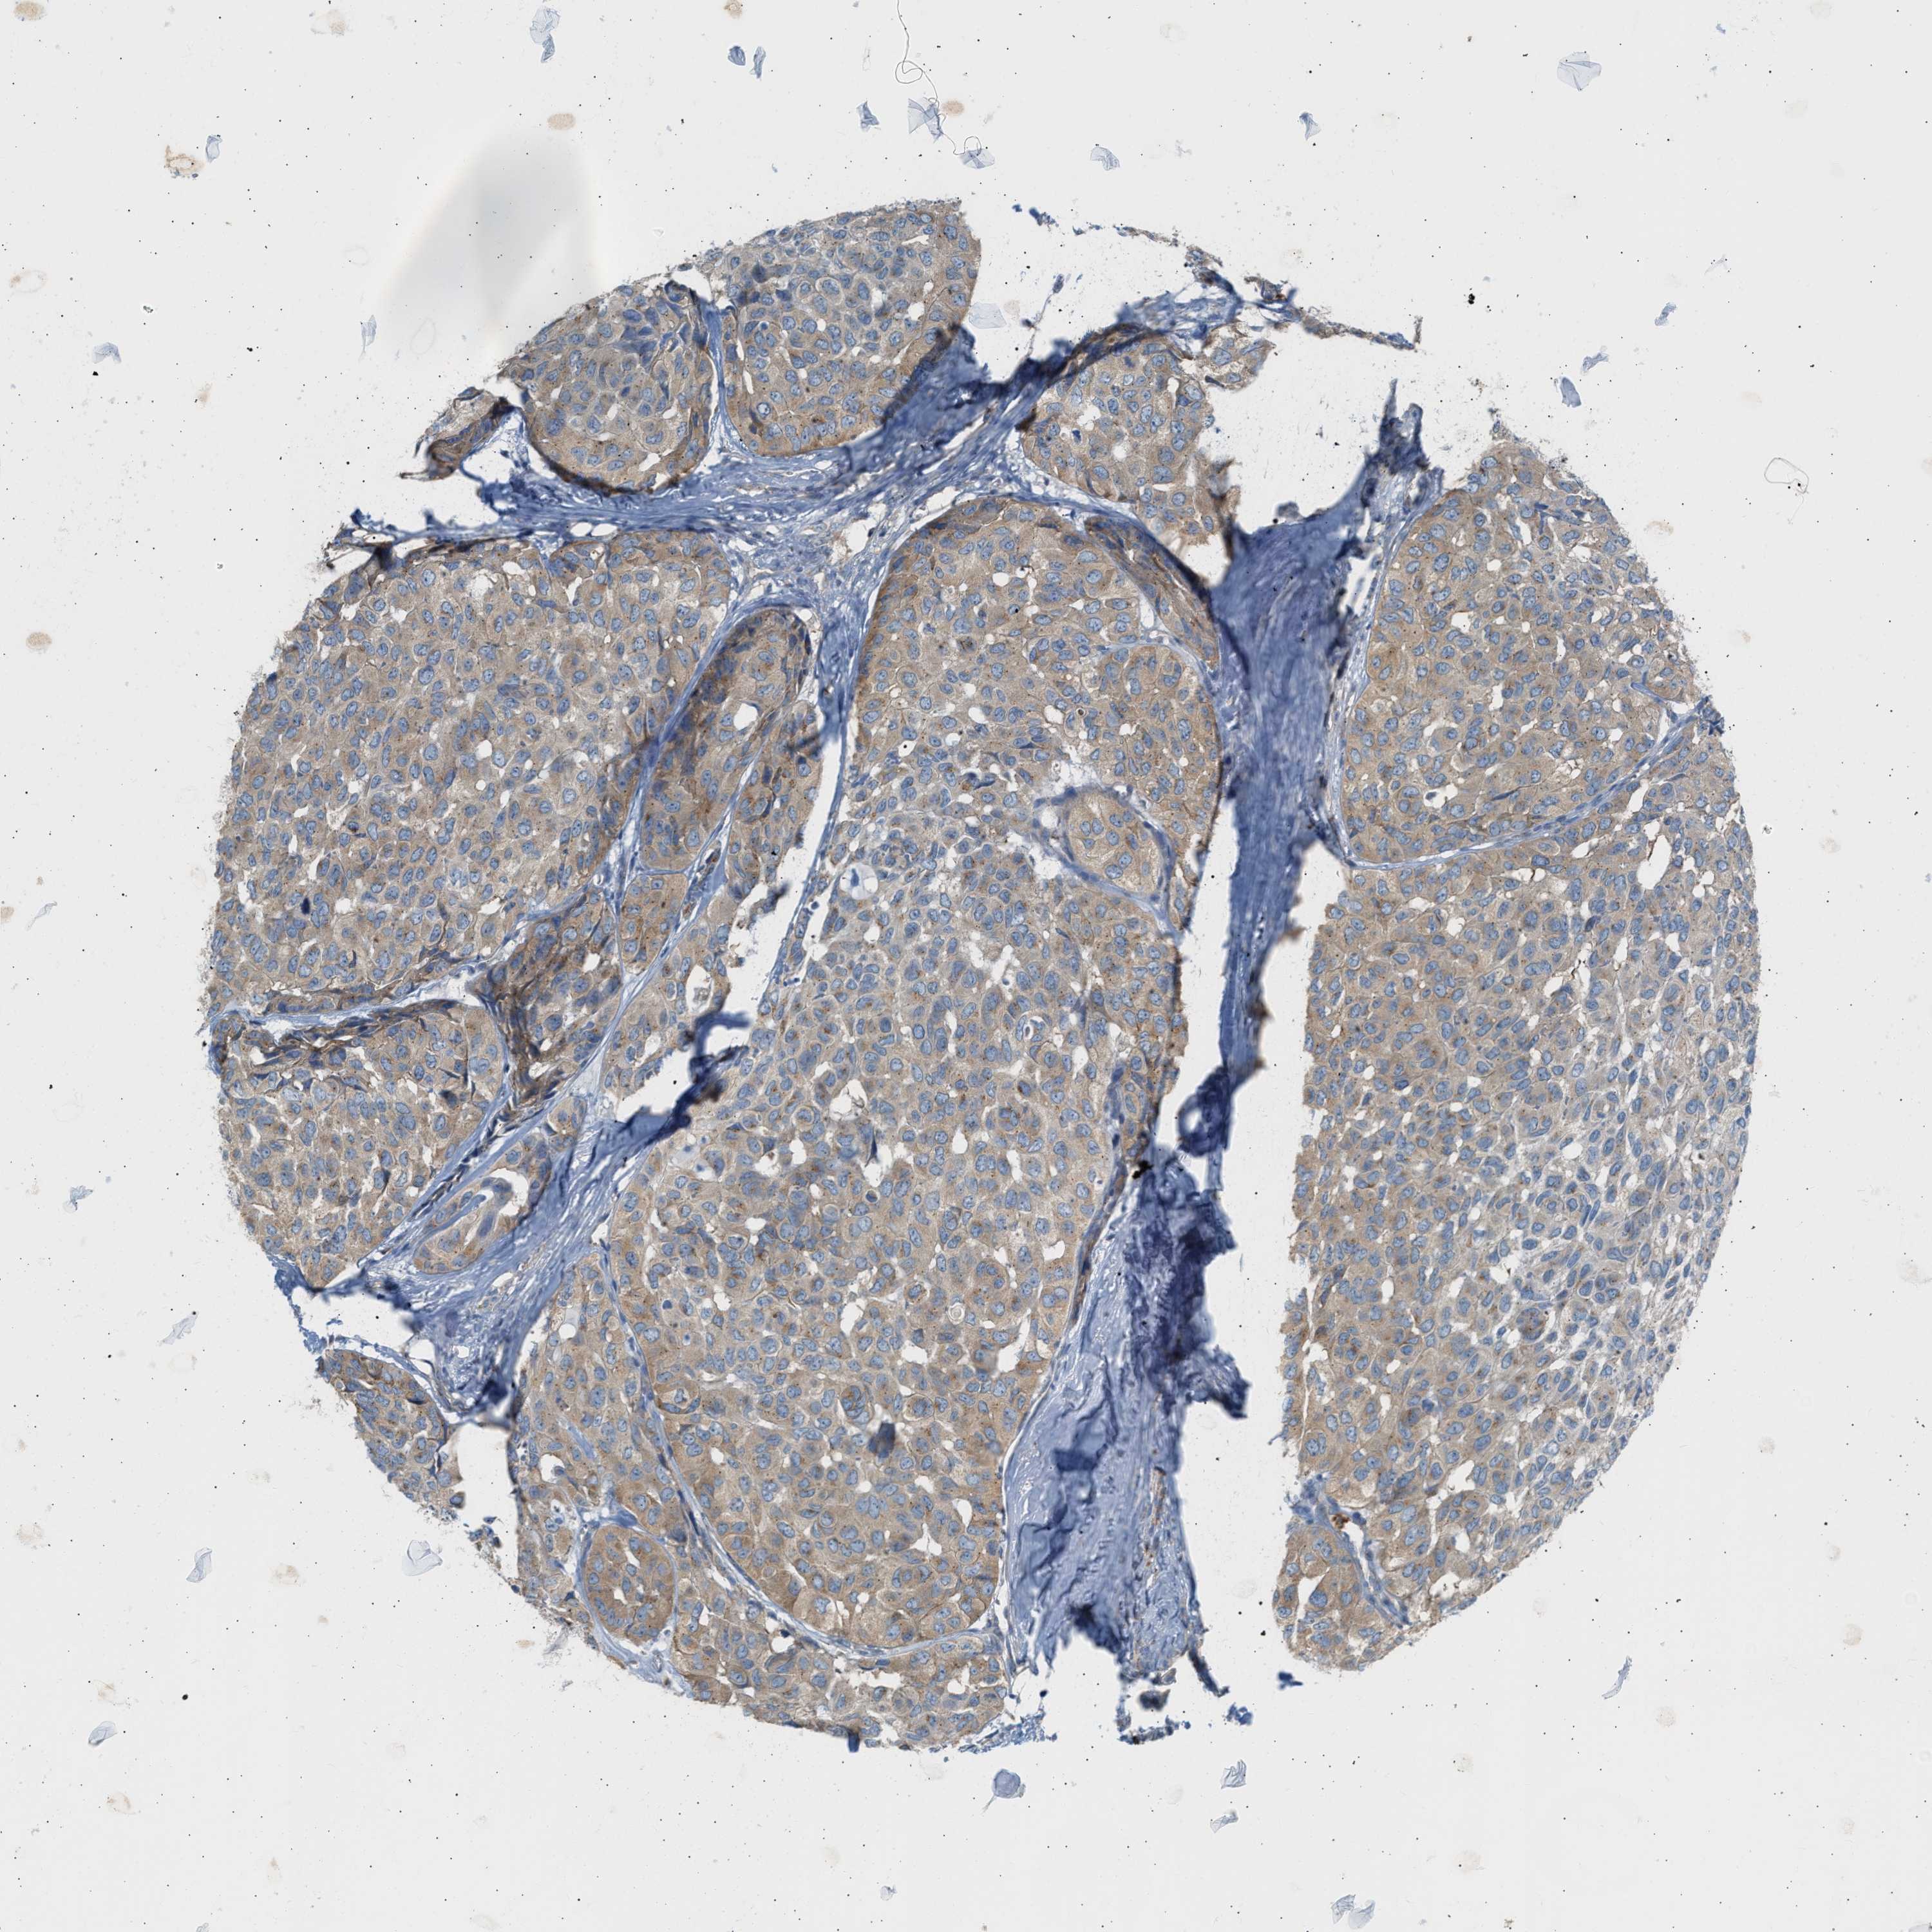

HEAD AND NECK CANCER - Protein expressioni

A mouse-over function shows sample information and annotation data. Click on an image to view it in a full screen mode. Samples can be filtered based on level of antibody staining by selecting one or several of the following categories: high, medium, low and not detected. The assay and annotation is described here.

Antibody stainingi

Antibody staining in the annotated cell types in the current human tissue is reported as not detected, low, medium, or high, based on conventional immunohistochemistry profiling in selected tissues. This score is based on the combination of the staining intensity and fraction of stained cells.

Each image is clickable and will lead to virtual microscopy that enables deeper exploration of all samples and also displays staining intensity scores, fraction scores and subcellular localization as well as patient and tissue information for each sample.

Antibody HPA019862

Staining

High

Medium

Low

Not detected

Intensity

Strong

Moderate

Weak

Negative

Quantity

>75%

75%-25%

<25%

None

Location

Nuclear

Cytoplasmic/membranous

Cytoplasmic/membranous,nuclear

Squamous cell carcinoma, NOS

Squamous cell carcinoma, metastatic, NOS

Adenocarcinoma, NOS